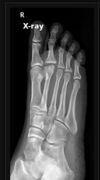

Doença de Freiberg